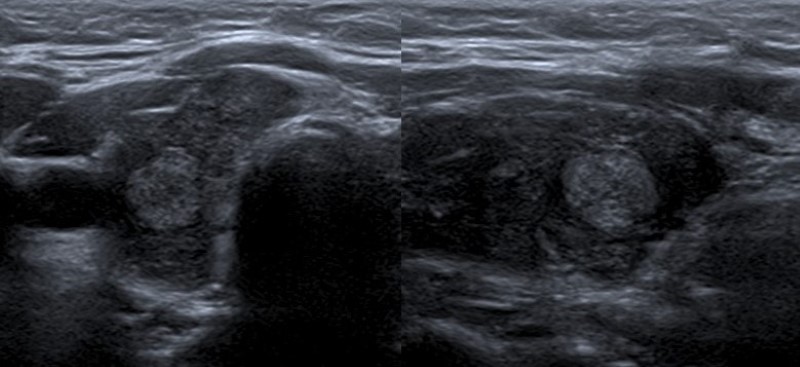

Composición

Describe el componente interno del nódulo, identificando la presencia de contenido sólido (Fig. 1) o quístico (Fig. 2), y en los casos de nódulos mixtos (Fig. 3) la proporción de cada uno (predominantemente sólido/ predominantemente quístico). Cuando se evalúa un nódulo parcialmente quístico es importante caracterizar su componente sólido indicando además si tiene localización central o periférica (esta última podría asociarse con mayor riesgo de malignidad)13.

Los nódulos completamente quísticos son considerados benignos2,14,15) y los sólidos se asocian mayormente a malignidad15,16, pero hay descriptos nódulos sólidos benignos, como así también nódulos confirmados como CPT con componente mixto2,15,17.

Existen otro tipo de nódulos, los espongiformes, que presentan un patrón mixto con múltiples quistes pequeños en su interior, y tienen un muy bajo riesgo de Malignidad2,13,14,18.